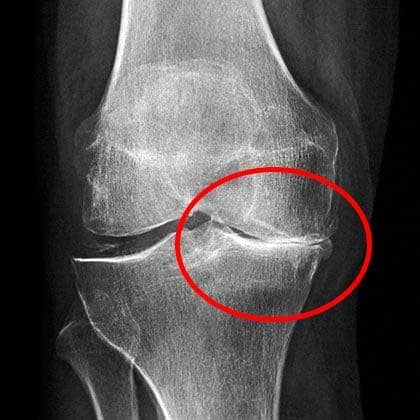

Placa de la rodilla

La radiografía mostró daños serios en mi rodilla.